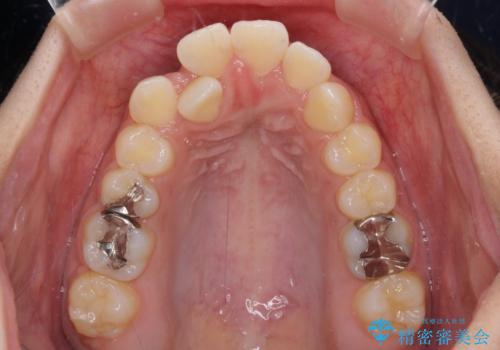

- 口元の突出感を気にして来院された患者様です。

デコボコと口元の突出感が認められたため、上下左右の第1小臼歯4本を抜歯してのワイヤー矯正を行うこととしました。

上顎歯列の横幅が狭く、下顎大臼歯の歯軸が舌側に倒れていたため、急速拡大装置により上顎骨を側方に拡大し、咬み合わせを改善することとしました。

上顎歯列幅を拡大したことで、デコボコを容易に解消することができるようになったため、抜歯により得られたスペースを口元の突出感改善に利用することができました。